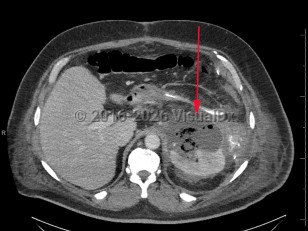

Perinephric abscess

A perinephric abscess is a collection of suppurative material in the perinephric space between the renal capsule and Gerota fascia. This condition is an uncommon complication of urinary tract infections, with incidence ranging from 1 to 10 cases for every 10 000 hospital admissions. Risk factors include diabetes mellitus (type 1, type 2) and renal stones.

Perinephric abscesses can be the consequence of pyonephrosis due to an obstruction nephrolith, recurrent pyelonephritis, or the rupture of a corticomedullary intra-nephric abscess. Perinephric abscess can also result from the spread of infection from extraperitoneal sites via hematogenous dissemination or from infection from adjacent structures such as the bowel, pancreas, and spine.